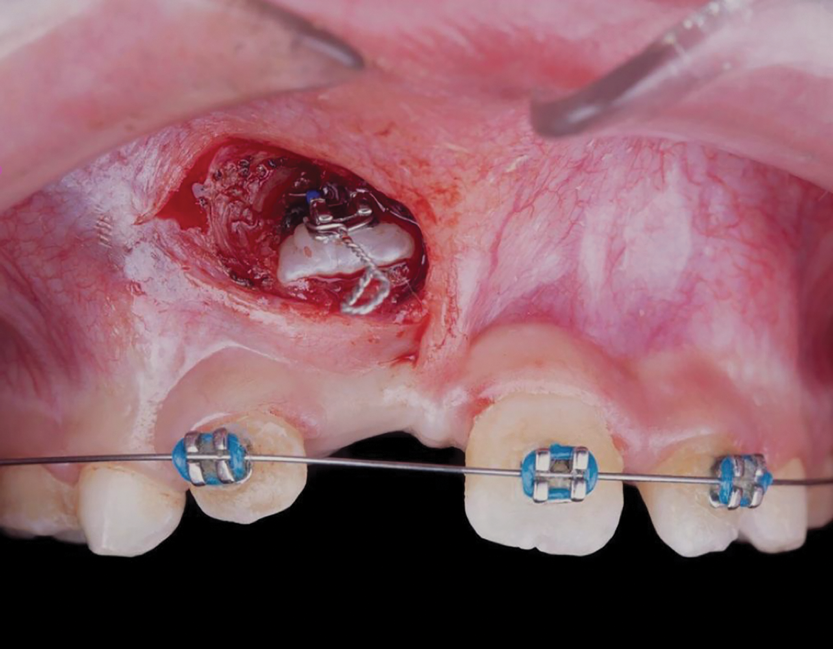

Fig 5. After performing an apical positioned flap, exposure of the impacted right central incisor was performed, frontal view (Fig 5) and occlusal view (Fig 6).

Figure 5

Fig 6. After performing an apical positioned flap, exposure of the impacted right central incisor was performed, frontal view (Fig 5) and occlusal view (Fig 6).

Figure 6

The maxillary right permanent centralincisor had a delayed eruption of 1½ years compared to its homologous incisor, and it was anteriorly displaced due to insufficient space in the premaxilla. Removal of the maxillary deciduous canines was indicated to unravel the crowding. An apically positioned flap of the impacted right central incisor was made to facilitate its eruption (Figure 5 and Figure 6). The case was worked up to plan an active phase l treatment, consisting of palatal expansion and the use of sectional fixed appliances in the upper arch. A transverse deficiency without posterior crossbite was identified, and therefore palatal expansion with a bonded expander was planned to widen the premaxilla (Figure 7 and Figure 8). A two-by-four fixed appliance system (brackets in the four maxillary anterior teeth and bands on the maxillary first molars) was used to align the maxillary teeth. The gingival margin of the retained maxillary right central incisor was slightly more apical than the left one, which erupted as expected (Figure 9 and Figure 10). Figure 11 shows a panoramic radiograph taken after completion of phase 1 treatment.